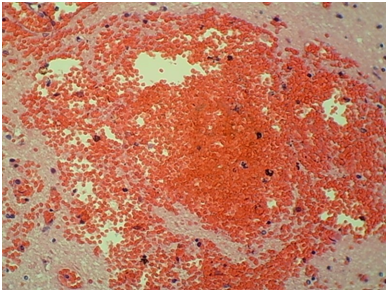

Autopsy of the decedent demonstrated disseminated invasive aspergillosis with multiple cavitating, necrotic, hemorrhagic, friable, soft, red and yellow-white lesions in both lungs (Figure 1), severe pericardial and pleural adhesions of the lungs, and hemorrhagic and cavitating soft masses in cerebrum (Figure 2) and cerebellum. Histologic examination of lungs revealed necrotizing pneumonia with sharply delineated rounded foci with hemorrhagic borders. Alveoli are filled with neutrophilic exudates with breakdown of the alveolar septa and formation of abscesses (Figure 3). In the brain there were multiple cavitating, hemorrhagic, friable, necrotic, soft yellow lesions. Microscopic sections demonstrated red blood cells and inflammatory cells in the involved area (Figure 4). GMS staining showed septate hyphae that branched dichotomously at acute angles, consistent with Aspergillus fungus (Figures 5&6). The fungal colonies were confined to the necrotic material and appeared as branching, slender, septate hyphae (Figures 5&6). There was no evidence of infection of the heart, pancreas, kidneys, liver, spleen, or adrenal glands.

Figure 2 Coronal section of brain with necrotic, hemorrhagic, friable, soft, red and yellow-white lesions.